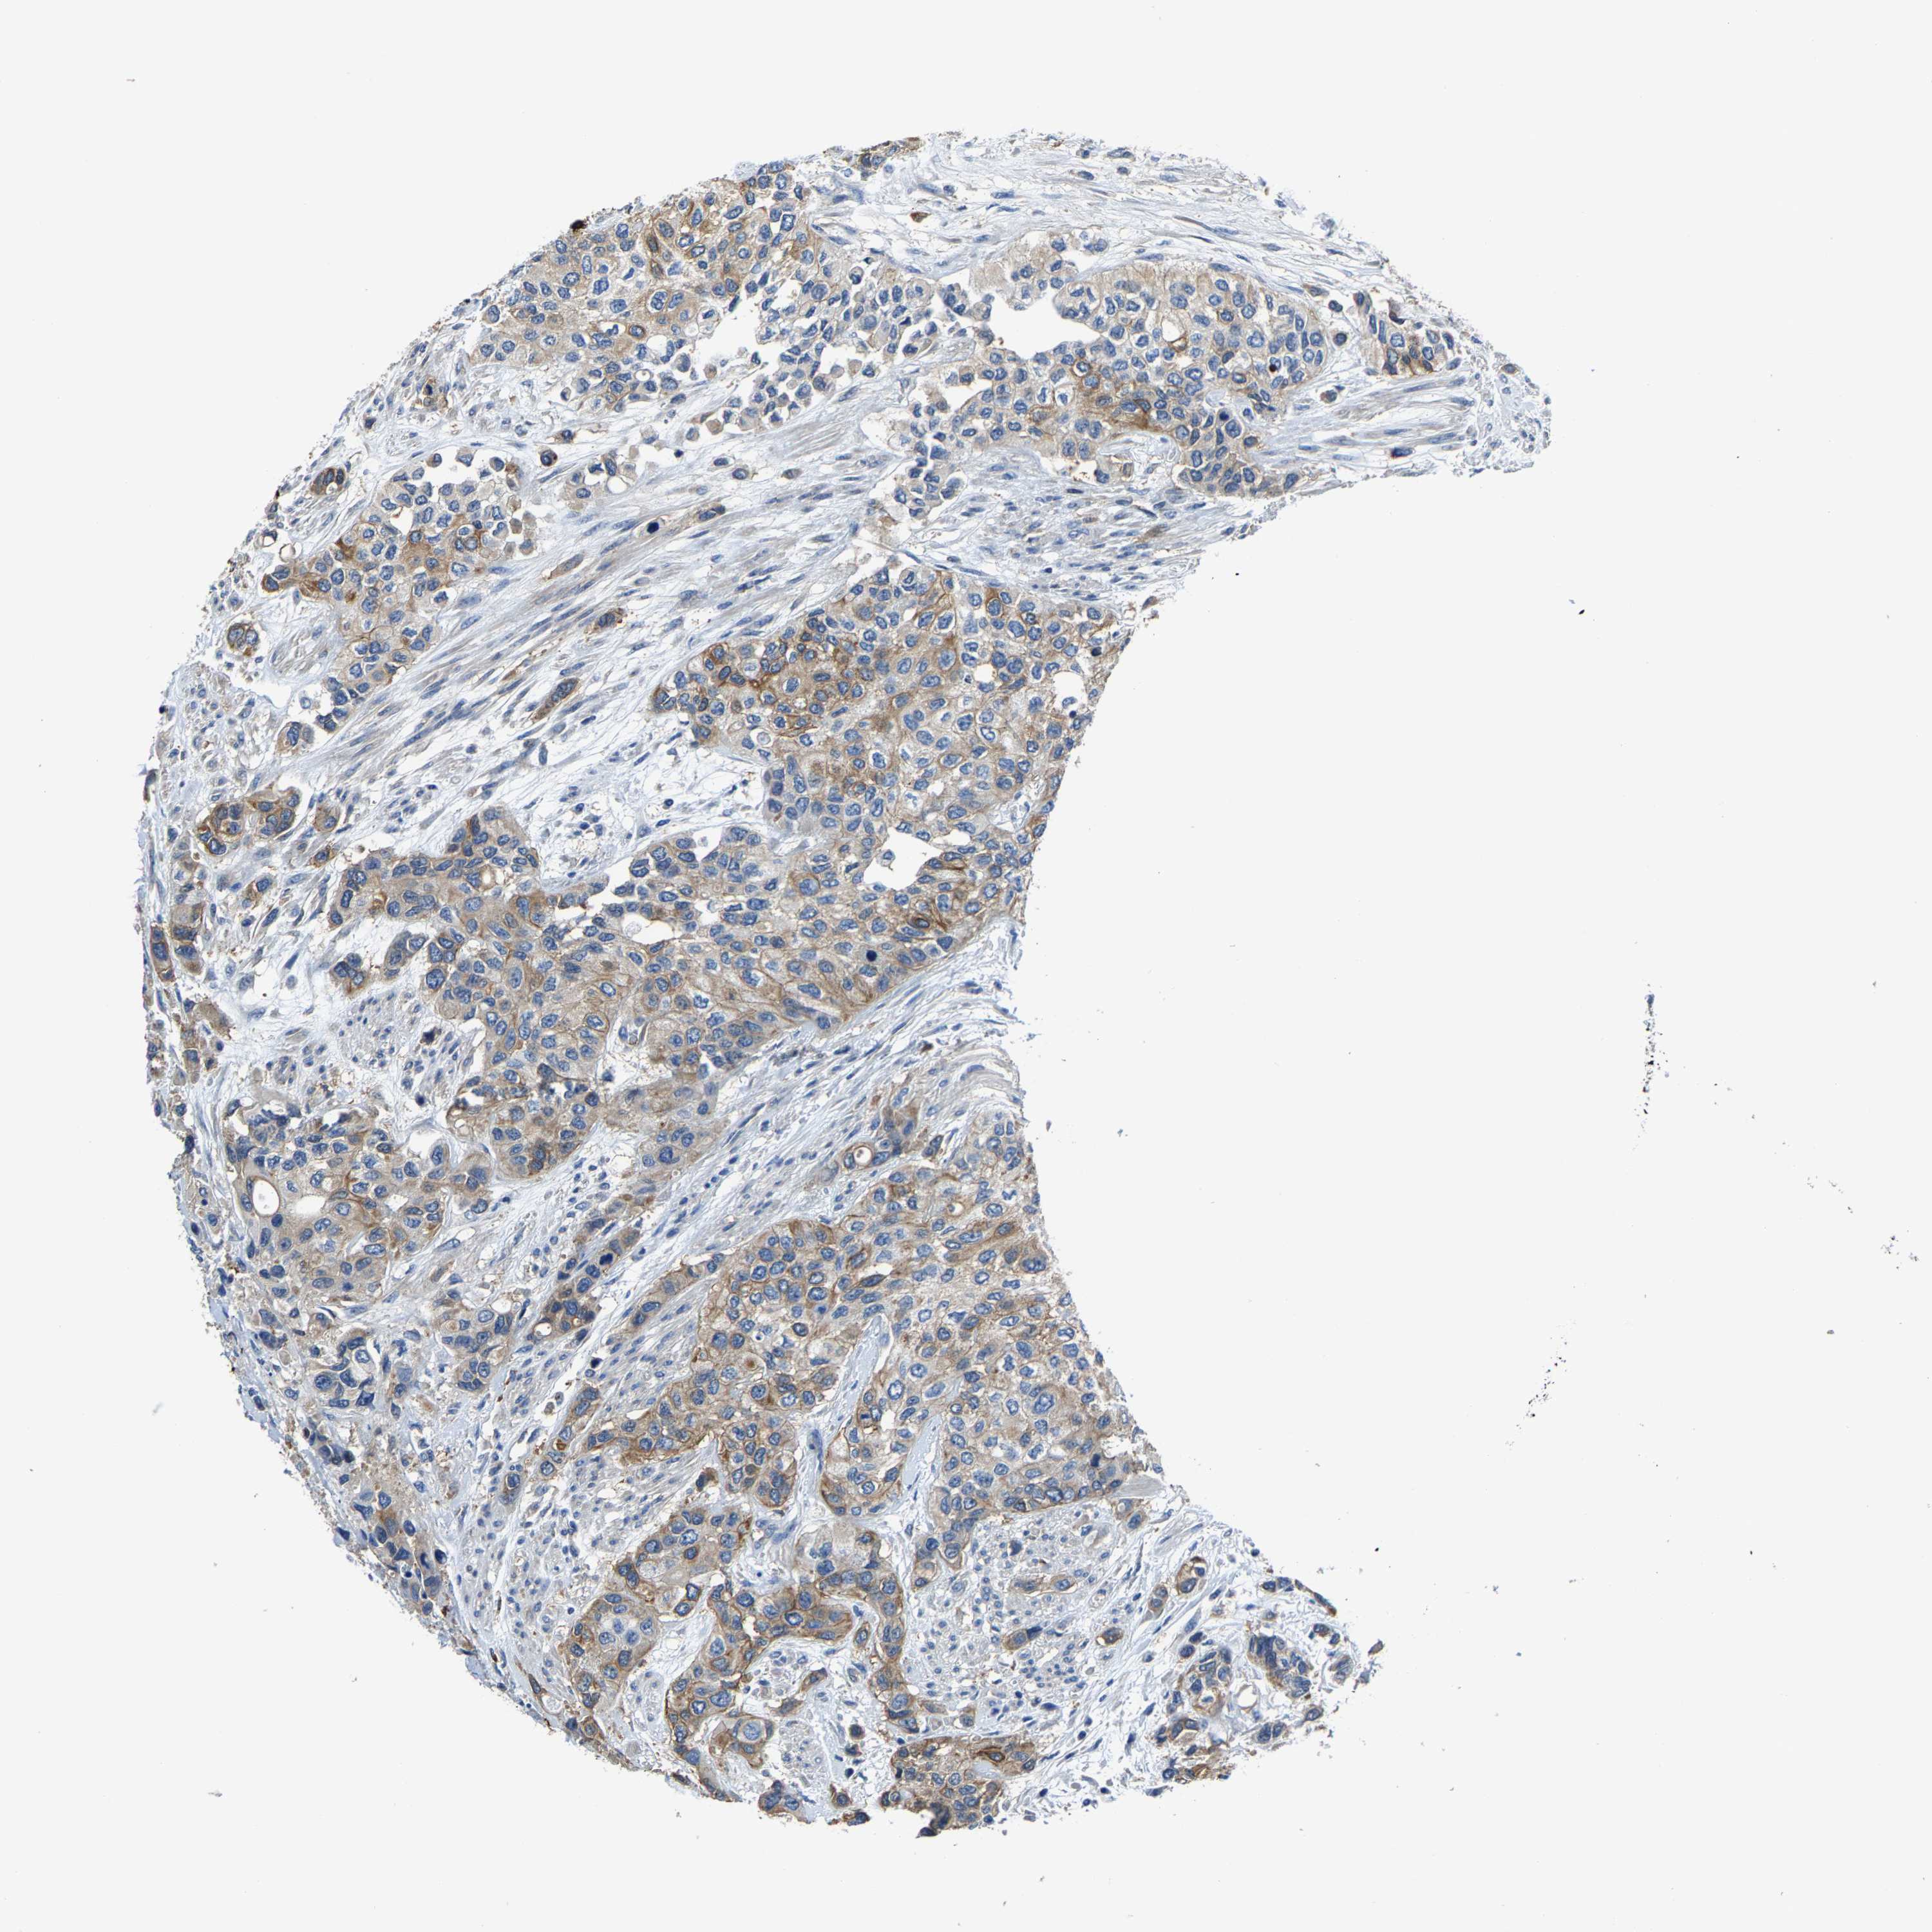

UROTHELIAL CANCER - Protein expressioni

A mouse-over function shows sample information and annotation data. Click on an image to view it in a full screen mode. Samples can be filtered based on level of antibody staining by selecting one or several of the following categories: high, medium, low and not detected. The assay and annotation is described here.

Note that samples used for immunohistochemistry by the Human Protein Atlas do not correspond to samples in the TCGA dataset.

Antibody stainingi

Antibody staining in the annotated cell types in the current human tissue is reported as not detected, low, medium, or high, based on conventional immunohistochemistry profiling in selected tissues. This score is based on the combination of the staining intensity and fraction of stained cells.

Each image is clickable and will lead to virtual microscopy that enables deeper exploration of all samples and also displays staining intensity scores, fraction scores and subcellular localization as well as patient and tissue information for each sample.

Antibody HPA019805

Antibody HPA020599

Antibody CAB004605

Staining

High

Medium

Low

Not detected

Intensity

Strong

Moderate

Weak

Negative

Quantity

>75%

75%-25%

<25%

None

Location

Nuclear

Cytoplasmic/membranous

Cytoplasmic/membranous,nuclear

Urothelial carcinoma, Low grade

Urothelial carcinoma, High grade